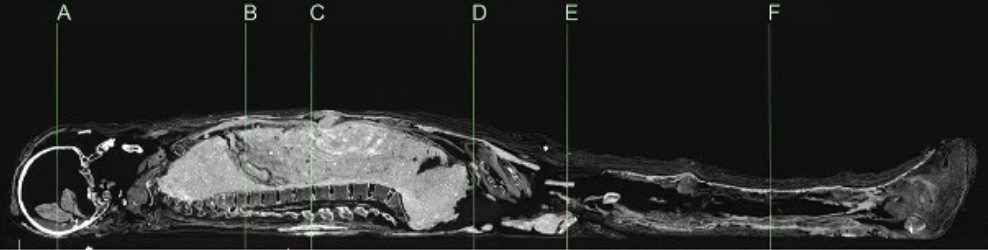

Các nhà khoa học Australia mới tiến hành chụp CT và xác định niên đại bằng phương pháp carbon phóng xạ cho một xác ướp Ai Cập và cỗ quan tài. Hiện chúng được lưu giữ và bảo quản tại Đại học Sydney.

Kết quả kiểm tra cho thấy xác ướp người phụ nữ có niên đại vào khoảng năm 1200 trước Công nguyên.

Trong khi đó, chiếc quan tài chứa xác ướp có niên đại vào khoảng năm 1000 trước Công nguyên.

Điều này đồng nghĩa với việc chiếc quan tài và xác ướp có niên đại không trùng khớp. Thi hài người phụ nữ có niên đại lớn hơn cỗ quan tài khoảng 200 năm.

Xác ướp người phụ nữ này được bọc trong một lớp bùn. Kỹ thuật này được cho là bắt chước theo phong tục mai táng của hoàng gia Ai Cập thời cổ đại.